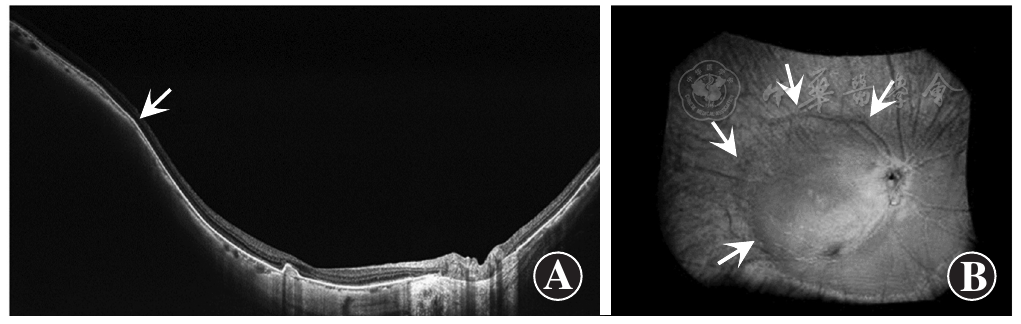

鸡在孵化后第1天通过缝合眼睑进行单眼形觉剥夺,8周后出现类似漆裂纹的病变[72](图1A)。与人类相似,这些病变往往是水平方向的,这可能是由于视网膜垂直方向的梳状血管结构。血管铸型表明漆裂纹没有明显的分界线。中间有一间隙,缺乏Bruch膜和脉络膜毛细血管层。这一间隙被脉络膜毛细血管密度降低的区域所包围,可能是由于血管床张力增加导致的萎缩(图1B)。此外,还可以看到大的脉络膜血管跨过间隙。RPE的增生和集聚(图1C),表明漆裂纹已经形成了一段时间,RPE有足够的时间做出反应。

Rge鸡在孵化后45 d就会出现漆裂纹[76](图2A)。组织学图片显示Bruch膜破裂,与周围结构完整的区域相比缺乏RPE(图2B)。

研究表明,病理性近视患者的漆裂纹往往因长度伸长、数量增加或进展为局限性萎缩而恶化[71,77,78]。有趣的是,鸡的模型也出现类似的进展模式。在图3中,与图2所示的8周龄鸡眼相比,50周龄的鸡眼睑缝合后出现了更多的漆裂纹和明显的眼轴伸长。虽然在长期观察眼睑缝合鸡的过程中未形成明显的局限性萎缩,但134周龄的rge鸡出现了类似局限性萎缩的环形病变(图3)。病变部位的OCT图像显示组织变薄和巩膜后弓状区域,这与病理性近视患者的局限性脉络膜视网膜萎缩相一致。这一发现表明,这2种特征可能具有相似的病理生理学特征,rge鸡可能是研究该病合适的动物模型。

如图3C所示,134周龄rge鸡的眼OCT图像显示,Bruch膜缺损区域巩膜向外隆起。由于巩膜移位的程度有限,很难断定这些巩膜变形一定是葡萄肿。然而,似乎有理由认为这可能是葡萄肿形成过渡的早期阶段。需要进行更长时间的观察,以监测巩膜变形的发展。

组织学切片和MRI检查显示,LRP2基因敲除小鼠模型分别在第15天和第21天出现眼轴增长和后巩膜葡萄肿(图4A,B)。脉络膜和RPE在葡萄肿边缘分离,这2层逐渐变薄,在进入视盘前消失。这些图像上不能清楚地识别Bruch膜。此外,视网膜明显变薄,在整个检测区域可见固缩的细胞体。这一发现表明,在这个模型中,有明显与视盘旁葡萄肿范围相对应的视盘旁萎缩区。这种构型与病理性近视患者的视盘周围γ区的后隆起相一致(图4C)[97]。